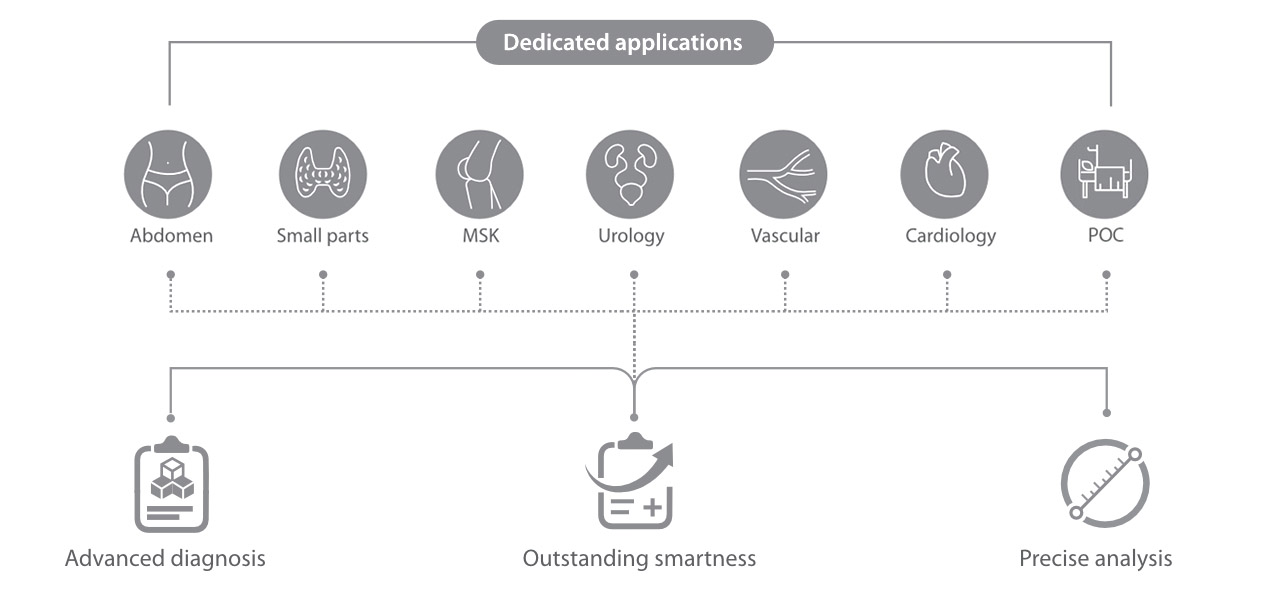

Das Resona I9 weist umfassende klinische Lösungen für spezielle Anwendungen auf. Auf der Grundlage gründlicher Analysen verschiedener klinischer Szenarien liefert es Innovationen, die den Benutzenden herausragende Klarheit, außergewöhnliche Intelligenz und eine erhöhte Diagnosesicherheit bieten.